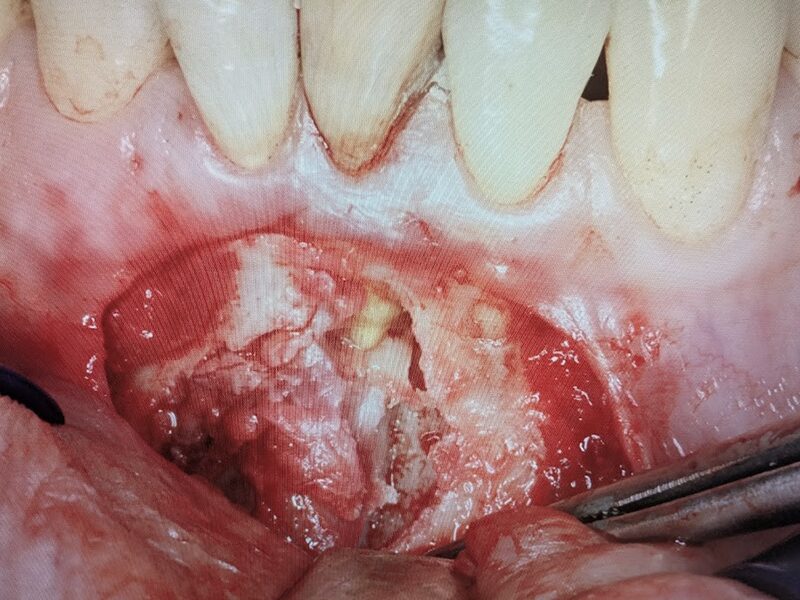

切開を実施いたします。

歯肉粘膜骨膜弁を剥離していきます。嚢胞壁は骨膜と癒着していため、鈍的に剥離を進めます。できるだけ嚢胞壁を壊さないようにします。

骨内の嚢胞にアプローチします。ガーゼで鈍的に剥離します。

骨内と嚢胞が分離してきています。上方に病巣の原因である歯根の先端が確認されました。

嚢胞壁を壊さないように骨から分離を行います。

骨内で嚢胞の剥離を進めます。